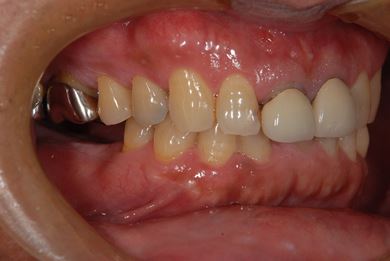

インプラントの症例写真 IMPLANT

インプラント治療

| 性別/年齢 | 男性 / 59歳 | ||||||||||||||||||||||||||||||||

| 主訴 | インプラント治療を検討中。 | ||||||||||||||||||||||||||||||||

| 治療方針 | 欠損部分インプラント治療により、機能的・審美的回復を行う。 | ||||||||||||||||||||||||||||||||

| 治療内容 | インプラント2本、ハイブリッドセラミック2本 | ||||||||||||||||||||||||||||||||

| 総治療費 | 738,675円 | ||||||||||||||||||||||||||||||||

| 治療期間 | 8ヶ月 |